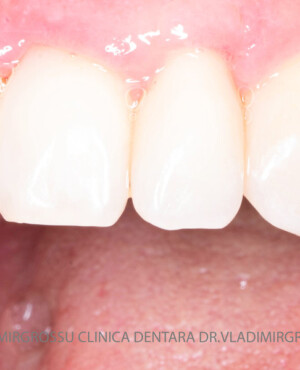

Aditia gingivală este o procedură chirurgicală ce corectează diverse probleme estetice și funcționale, cum ar fi recesiunea gingivală. În implantologia modernă, aditia de țesut moale este utilizată aproape în fiecare intervenție de inserție a implantului dentar pentru a asigura un aspect estetic natural și o bună integrare a implantului în cavitatea bucală.